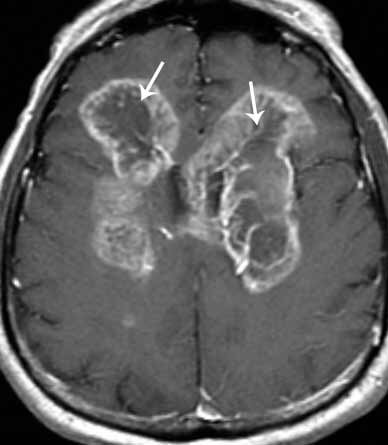

Магнитно-резонансная и компьютерная томография – наиболее информативные методы исследования. МРТ головного мозга позволяет выявить очаг опухоли или перифокального отека как реакцию на опухолевый рост. МРТ безопасный для пациента метод, так как во время сканирования организм не облучается. У магнитной томографии есть недостаток: снимок рака мозга не позволяет отличать доброкачественные опухоли от злокачественных. Рак мозга на МРТ выглядит как очаг ограниченный темный очаг, окруженный воспалительным валом.

Разновидности МРТ, такие как SWI/SWAN, трактогарфия или МРС позволяют выполнить дифференциальную диагностику между злокачественными опухолями и доброкачественными. Они также способны установить степень злокачественности и оценить эффективность лечения.

Для уточнения и детализации кровотока используют контрастирование в режиме ангиографии. Компьютерная томография позволяет оценить степень повреждения гематоэнцефалического барьера. Ангиография всегда используется, если есть подозрение на опухоль.